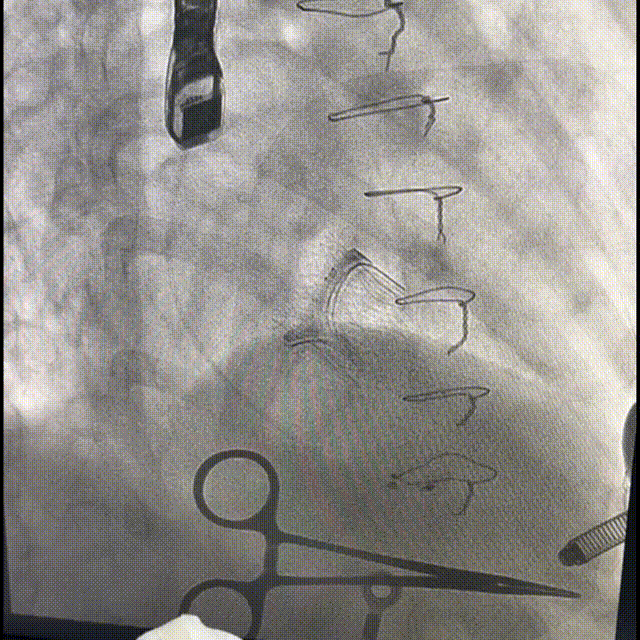

术中影像

直头导丝配合鞘芯跨瓣,最终将加硬导丝盘置于左心房输送系统入心尖并跨瓣,同轴良好,调整瓣膜上1/4与瓣环平面平齐,瓣膜先预释放三分之一,后180bpm起博下完全释放瓣膜

瓣膜位置良好,无张力脱钩

输送系统在心腔内完全闭合后撤出,配合收紧荷包

二尖瓣打开通畅,无瓣周漏

二尖瓣

最大流速:87.4cm/s

平均压差:3mmHg